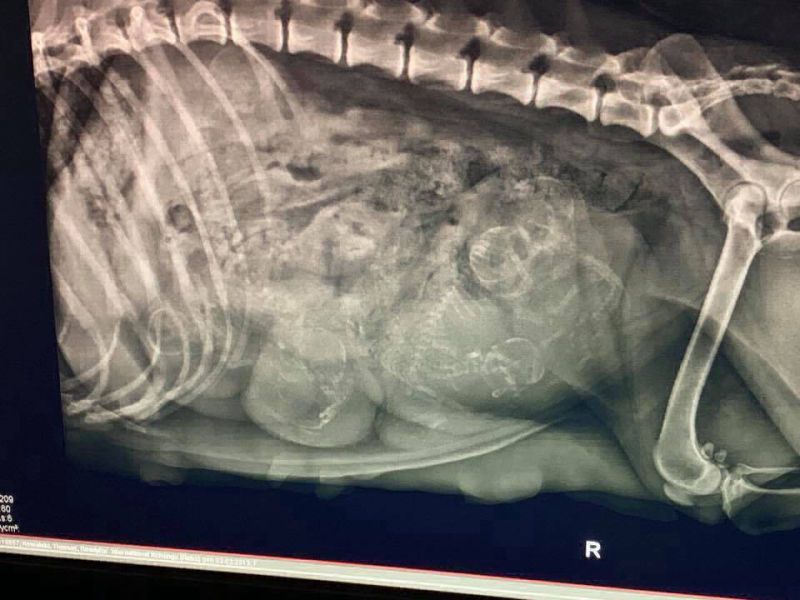

Hündin: "Reba" Readyfor `Nternational Xchang

19.01.2019

heute hat Reba 6 gesunde Welpen (3m/3w) zur Welt gebracht